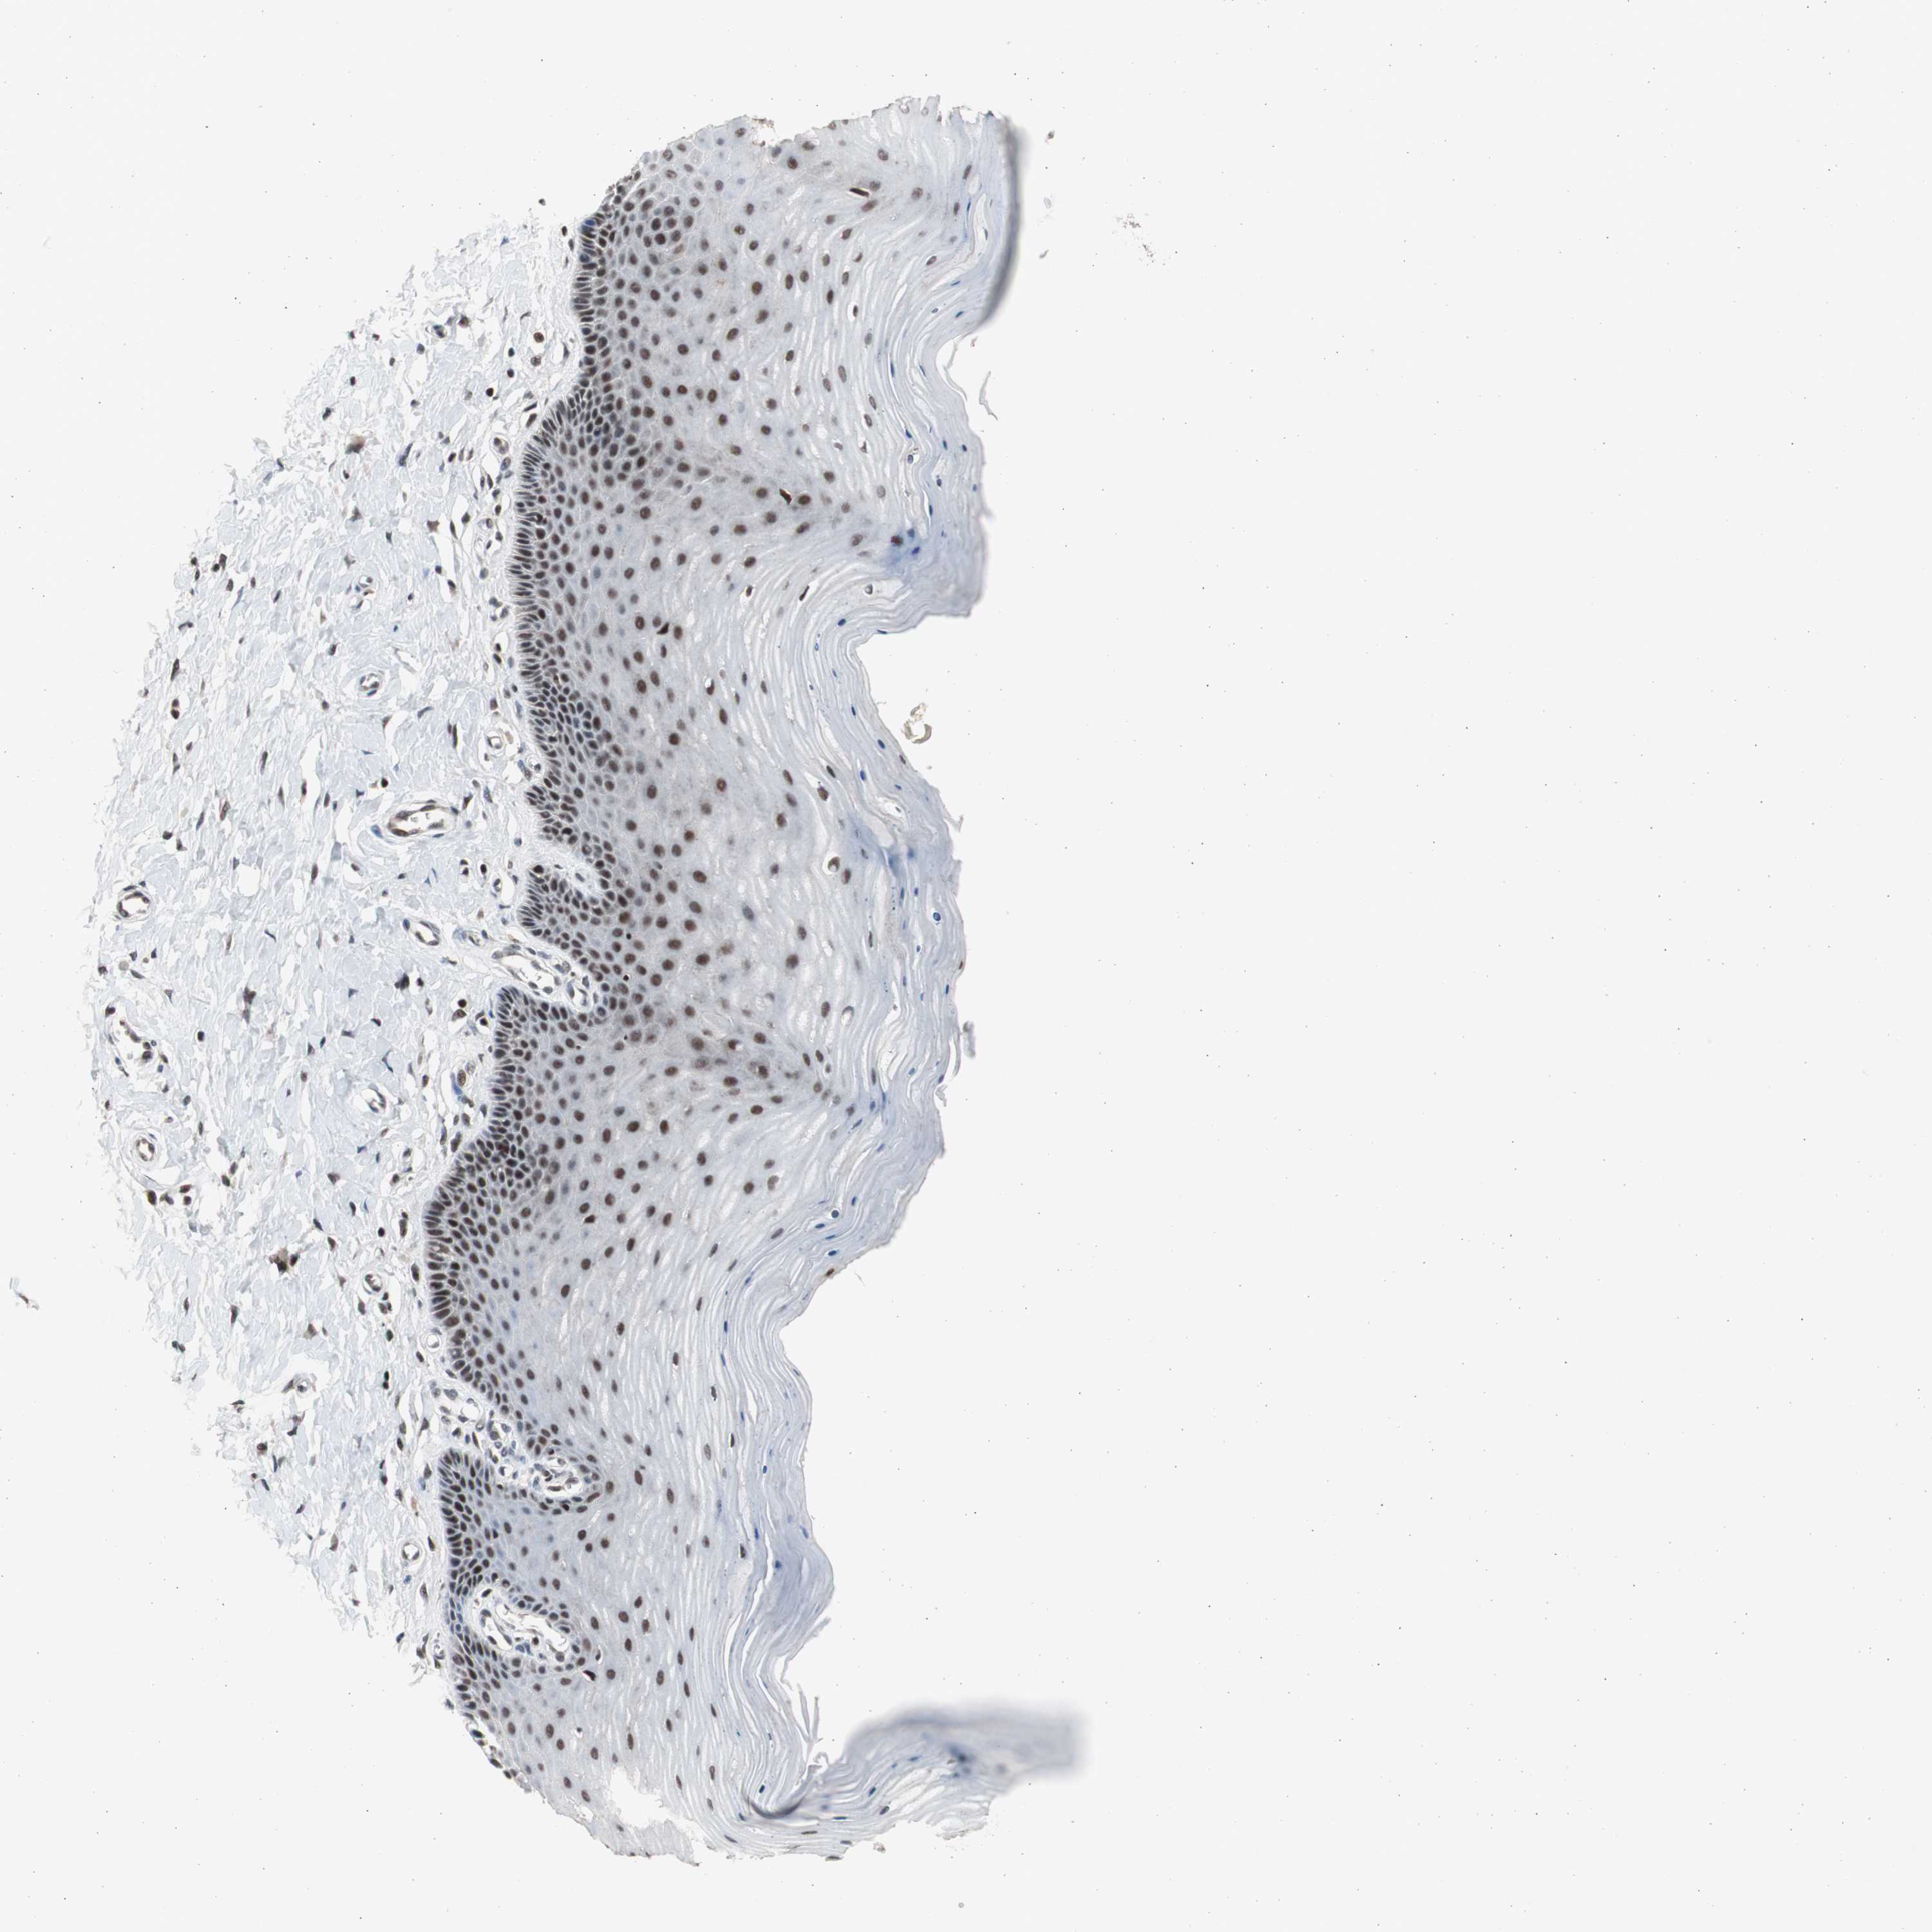

CERVIX - Antibody stainingi

Antibody staining in the annotated cell types in the current human tissue is reported as not detected, low, medium, or high, based on conventional immunohistochemistry profiling in selected tissues. This score is based on the combination of the staining intensity and fraction of stained cells.

Each image is clickable and will lead to virtual microscopy that enables deeper exploration of all samples and also displays staining intensity scores, fraction scores and subcellular localization as well as patient and tissue information for each sample.

Antibody HPA006914Antibody CAB004563

Glandular cells HighLow

Squamous epithelial cells HighHigh